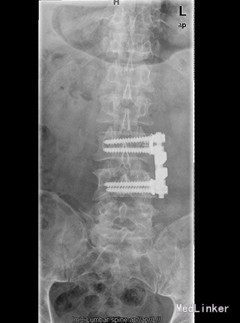

初步诊断:腰4椎体骨质破坏:结核?肿瘤? 诊疗计划:经前路腰4椎体部分切除,椎管减压,取自体髂骨植骨融合,Antares内固定术

术中见腰4椎体骨质破坏,其内可见空腔形成,周围骨质硬化,左侧椎旁椎体空腔内可见少量干酪样坏死组织,腰3、4椎间盘破坏、碎裂,部分组织突入椎管,压迫硬膜囊,取坏死组织术中冰冻切片示:肉芽肿性炎症伴坏死。